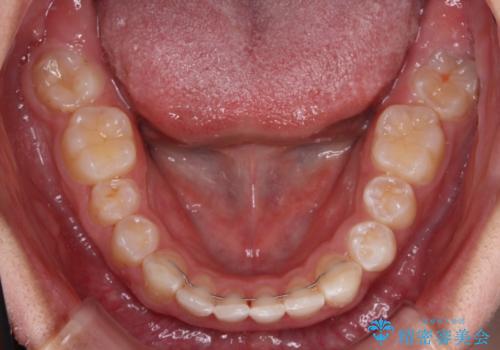

下顎前歯が全て隠れてしまうほどの深い咬合で、左右の奥歯は1歯対1歯で咬み合う状態でした。

前方に移動している上顎臼歯を補助装置にて遠心移動させることで1歯対2歯の臼歯咬合を目指し、同時に深い咬合を改善していくこととしました。

このような咬み合わせの場合、治療期間は2年以上がかかることが一般的で、3年程度かかることもありえるケースです。

強く深い咬み合わせにより下顎装置は頻繁に脱離するため、治療期間が長くなりますが、予定通りに終了させることができました。